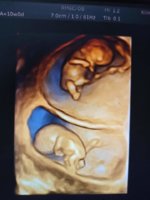

Ама од почетокот имам слика од моите ептен што си ја сакам, еве ќе ви ја покажам. Другите сите не се за пред јавност, само за очите на мама се, а на мама најубави и се какви и да се :D received_1326596267858105.jpeg

@AugusTina! Што убаво заедно ти ги сликале :inlove::inlove:

Ме топите со близнациве